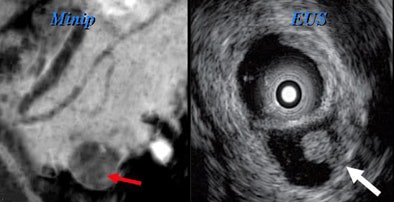

"There's no way to distinguish them, so by the time your cyst has exceeded 4 cm, you've pretty much bought yourself a needle aspiration," Jeffrey said. Esophageal EUS-guided fine-needle aspiration is the key to differentiating these small cyst types and in fact the way to evaluate most lesions larger than 3 cm in diameter.

"If they're greater than 3 cm, we're going to want to go on to needle aspiration, but when they're small -- and particularly if we can identify distinctive morphological features -- we can be very comfortable following these with imaging [MDCT, EUS, or magnetic resonance cholangiopancreatography (MRCP)]," he said. "Cystic cancers are rare, but they invariably have solid components or increase [in size] over time."

There are no data on the optimal follow-up time or imaging method (CT, EUS, or MRCP). However, several authorities have suggested a one-year follow-up interval for lesions smaller than 1 cm and a six-month follow-up for larger lesions, with follow-up directed at assessing size and the presence of internal solid tissue within the cyst, he said.

Researchers have also experimented with ethanol ablation under EUS guidance for cysts 1 cm and smaller, Jeffrey said of a pilot study from Massachusetts General Hospital in Boston. Gan et al found that in eight of 23 (35%) patients with complete follow-up, the cysts resolved completely, with evidence of epithelial ablation in five other patients who underwent surgical resection (Gastrointestinal Endoscopy, May 2005, Vol. 61:6, pp. 746-752).